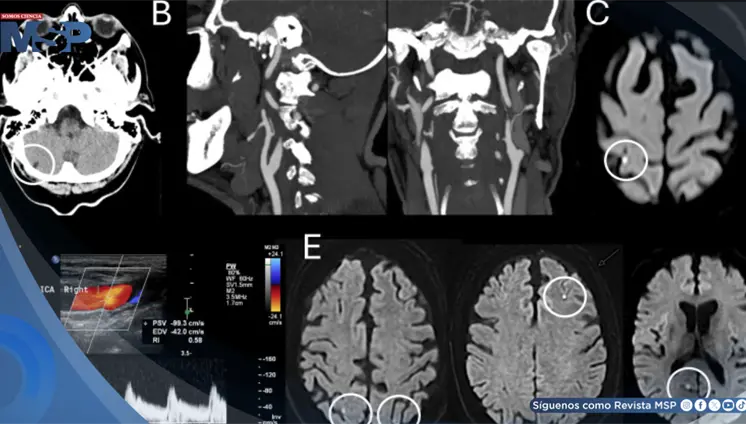

Síndrome de encefalopatía posterior reversible asociado a crisis hipertensiva con estado epiléptico